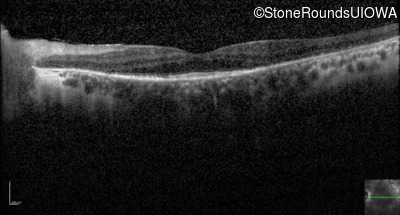

Optical Coherence Tomography - Left - 20/70 +1

Exemplar / OCT Stack